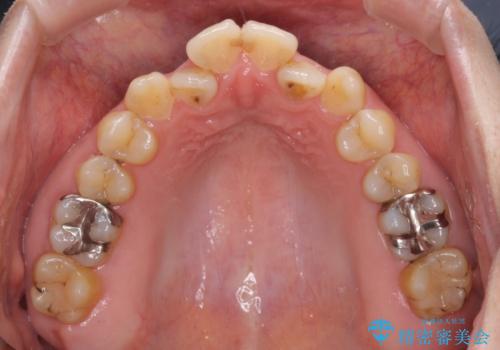

- 前歯のデコボコを気にして来院された患者様です。

前歯のデコボコはもちろん気になるところですが、舌の突出癖により上下前歯が非接触となっている状態でした。

上下前歯が非接触である開咬は、インビザラインによる治療がお勧めではありますが、しっかりと使う自信がないとのことで、ワイヤー装置にて治療を行うこととしました。

デコボコはあっという間に改善されましたが、開咬の改善に時間がかかりました。

舌の突出癖改善のトレーニングをしっかりと行っていただき、上下前歯が接触する咬み合わせを達成することができました。